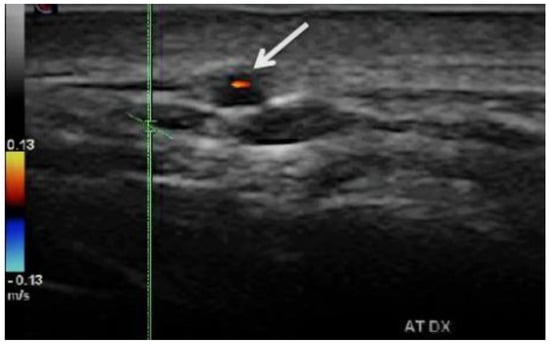

- “Dark halo” sign: An usually homogeneous, hypoechoic wall thickening surrounding the lumen of an inflamed artery. It is well outlined towards the luminal side, visible both in longitudinal and transverse planes, most commonly concentric in transverse.

- Compression sign. The thickened vessel wall remains visible upon compression by the ultrasound examiner; the wall swelling is hypoechogenic (in acute temporal arteritis), contrasting with the mid-echogenic to hyperechogenic surrounding tissue [38].